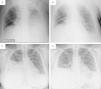

Case 1A 54-year-old man with a history of cervical spinal cord injury 28 years ago, with tetraparesis and chronic hypercapnic respiratory failure under nocturnal non-invasive ventilation (NIV), was hospitalized for sympathectomy due hyperhidrosis. The procedure was complicated by a left pneumothorax, and a chest tube was placed. Approximately 24h after chest tube removal, systemic inflammation was documented, and the chest radiograph showed a left pleural effusion, which thoracic ultrasound proved to be multiloculated (pleural fluid characteristics after thoracentesis were indicative of pleural infection). Despite antibiotics and the insertion of a new chest tube (Fig. 1A), the patient continued to present with fever, and pleural fluid drainage was very limited during subsequent days. Given the high patient surgical risks inherent to his comorbidities, combined intrapleural therapy (CIT) was started using a protocol similar to that explained by Rahman et al.,4 with 5mg dornase alfa (DNase) diluted in 45ml NaCl 0.9% and 10mg alteplase (fibrinolytic), diluted in 40ml NaCl 0.9% (both administered sequentially twice a day, for 3 consecutive days), clamping the drain for 1h following administration of each drug, allowing them to act. This resulted in a significant increase in pleural fluid drainage, and rapid clinical and radiological improvement (Fig. 1B). There were no complications associated with this treatment, and the patient was discharged 10 days after beginning CIT, without the need for any additional interventions.

Case 2A 41-year-old woman with no relevant past medical history, presented with right pleuritic pain, systemic inflammatory syndrome and evidence of loculated right pleural effusion in thoracic ultrasound. Thoracentesis was indicative of pleural infection, so she was given antibiotics, and a chest tube was placed (Fig. 1C). On subsequent days, pleural fluid drainage remained vestigial, and analytic inflammatory markers remained elevated. Thoracic surgery was not found to be emergent; consequently, CIT was undertaken, following a similar protocol as in Case 1, with comparable results (Fig. 1D). The patient was discharged 12 days after beginning intrapleural treatment, and no further drainage was needed. As a complication, she reported intense local pain during the instillation of the drugs, which was suitably controlled with systemic analgesia administered before subsequent procedures.